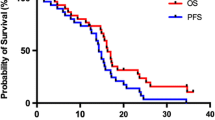

The median follow-up times for the hypo-IMRT/TMZ alone trial and the hypo-IMRT/TMZ/BEV trial were 13.9 and 14.7 months, respectively. Median PFS was increased by 3.4 months in the hypo-IMRT/TMZ/BEV trial, compared to the hypo-IMRT/TMZ alone trial (12.8 vs. 9.4 months, p = 0.58) (Fig. 1). PFS at 6 months was not significantly different between the two trials (84 and 83 %, respectively, p = 0.702). Median OS was the same in both trials at 16.3 months (Fig. 2).

At the time of data analysis for this report four patients treated on the hypo-IMRT/TMZ alone trial are still alive with a median OS of 65 months (range 42.1–66.8). Four patients treated on the hypo-IMRT/TMZ/BEV trial remain alive with a median OS of 32.7 months (range 10.5 – 34.7). Two year OS for the combined patient population was 25.5 %. Five year OS for the hypo-IMRT/TMZ alone trial was 12 %.

In the hypo-IMRT/TMZ/BEV trial we sought to evaluate the effect of bevacizumab in combination with hypo-IMRT and temozolomide on PFS survival as a primary endpoint, and OS and toxicity as secondary endpoints. This comparison study demonstrated a statistically non-significant increase in PFS with bevacizumab of 3.4 months (p = 0.39), and no difference in OS. Two recently published large randomized trials, the AVAGlio and RTOG 0825, have reported similar findings with standard fractionation radiation, temozolomide and BEV. The addition of bevacizumab improved progression free survival by 3.4–4.4 months, but had no effect on OS [22, 23].